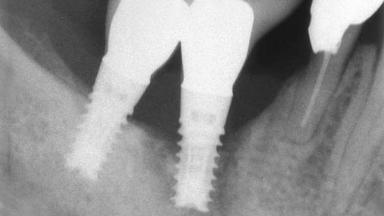

A 82-year-old female patient was referred to the Department of Oral Surgery and Stomatology at the University of Bern, Switzerland, for further diagnosis and treatment of growing discomfort in the right mandible (implant 45) and left maxilla (implant 23). The patient had had implants of various types inserted in the mandible and maxilla over the course of the previous three decades (in the 1980s and 1990s). The patient had received removable partial dentures on implants in the maxilla and on natural teeth in the mandible. The implants in the posterior right mandible had been restored with two splinted single crowns. The lower partial denture was not well tolerated by the patient and therefore had not been worn for over ten years. After insertion of the implants, there had been no complications for many years, but implants 45 and 46 as well as 23 had begun to exhibit signs of peri-implantitis with limited bone loss several years previously. The infection had been treated by the private practitioner, and bone loss around the three implants had not progressed until about half a year previously.